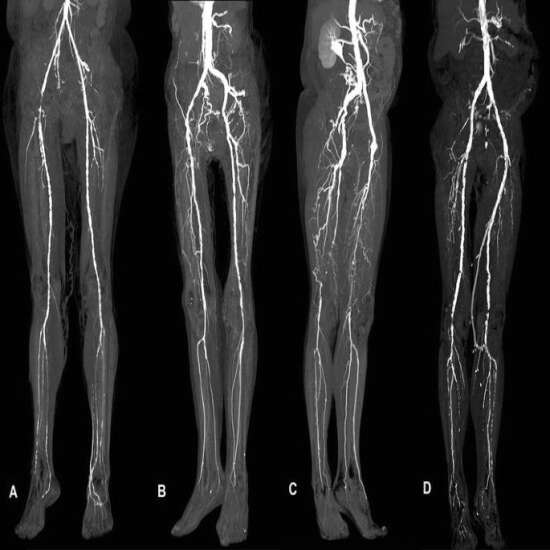

CT Peripheral Angiography is an imaging technique. It checks for blockages in the arteries that supply blood to your legs and feet but in some cases to arms and hands. It is very helpful for doctors to find the narrowed or blocked areas in the peripheral arteries.

CT (Computed tomography) screening of the  Peripheral Angiography is a non-invasive radiology test used to evaluate the condition of arteries and surrounding tissue. CT Peripheral Angiography is done to look for the conditions of the arteries and the surrounding area.